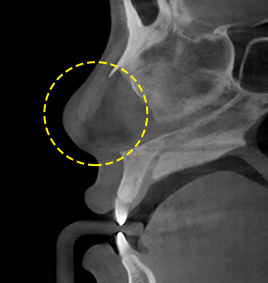

กรณีที่ 5ตอนที่วัสดุปลุกถ่ายโปนออกมาเป็นรูปตัวแอล

เราจะทำการจำแนกระดับการมองเห็นและตำแหน่งของวัสดุที่ปลูกถ่ายเอาไว้ได้อย่างแม่นยำ จากนั้นทหการถอดวัสดุปลูกถ่ายรูปตัวแอลออก แล้วแทนที่ด้วยวัสดุปลูกถ่ายรูปตัวไอ ตามด้วยการใช้กระดูกอ่อนปรับเปลี่ยนรูปทรงของปลายจมูก